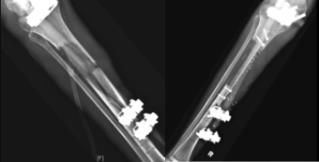

Free vascularized fibula graft filling a large tibial defect